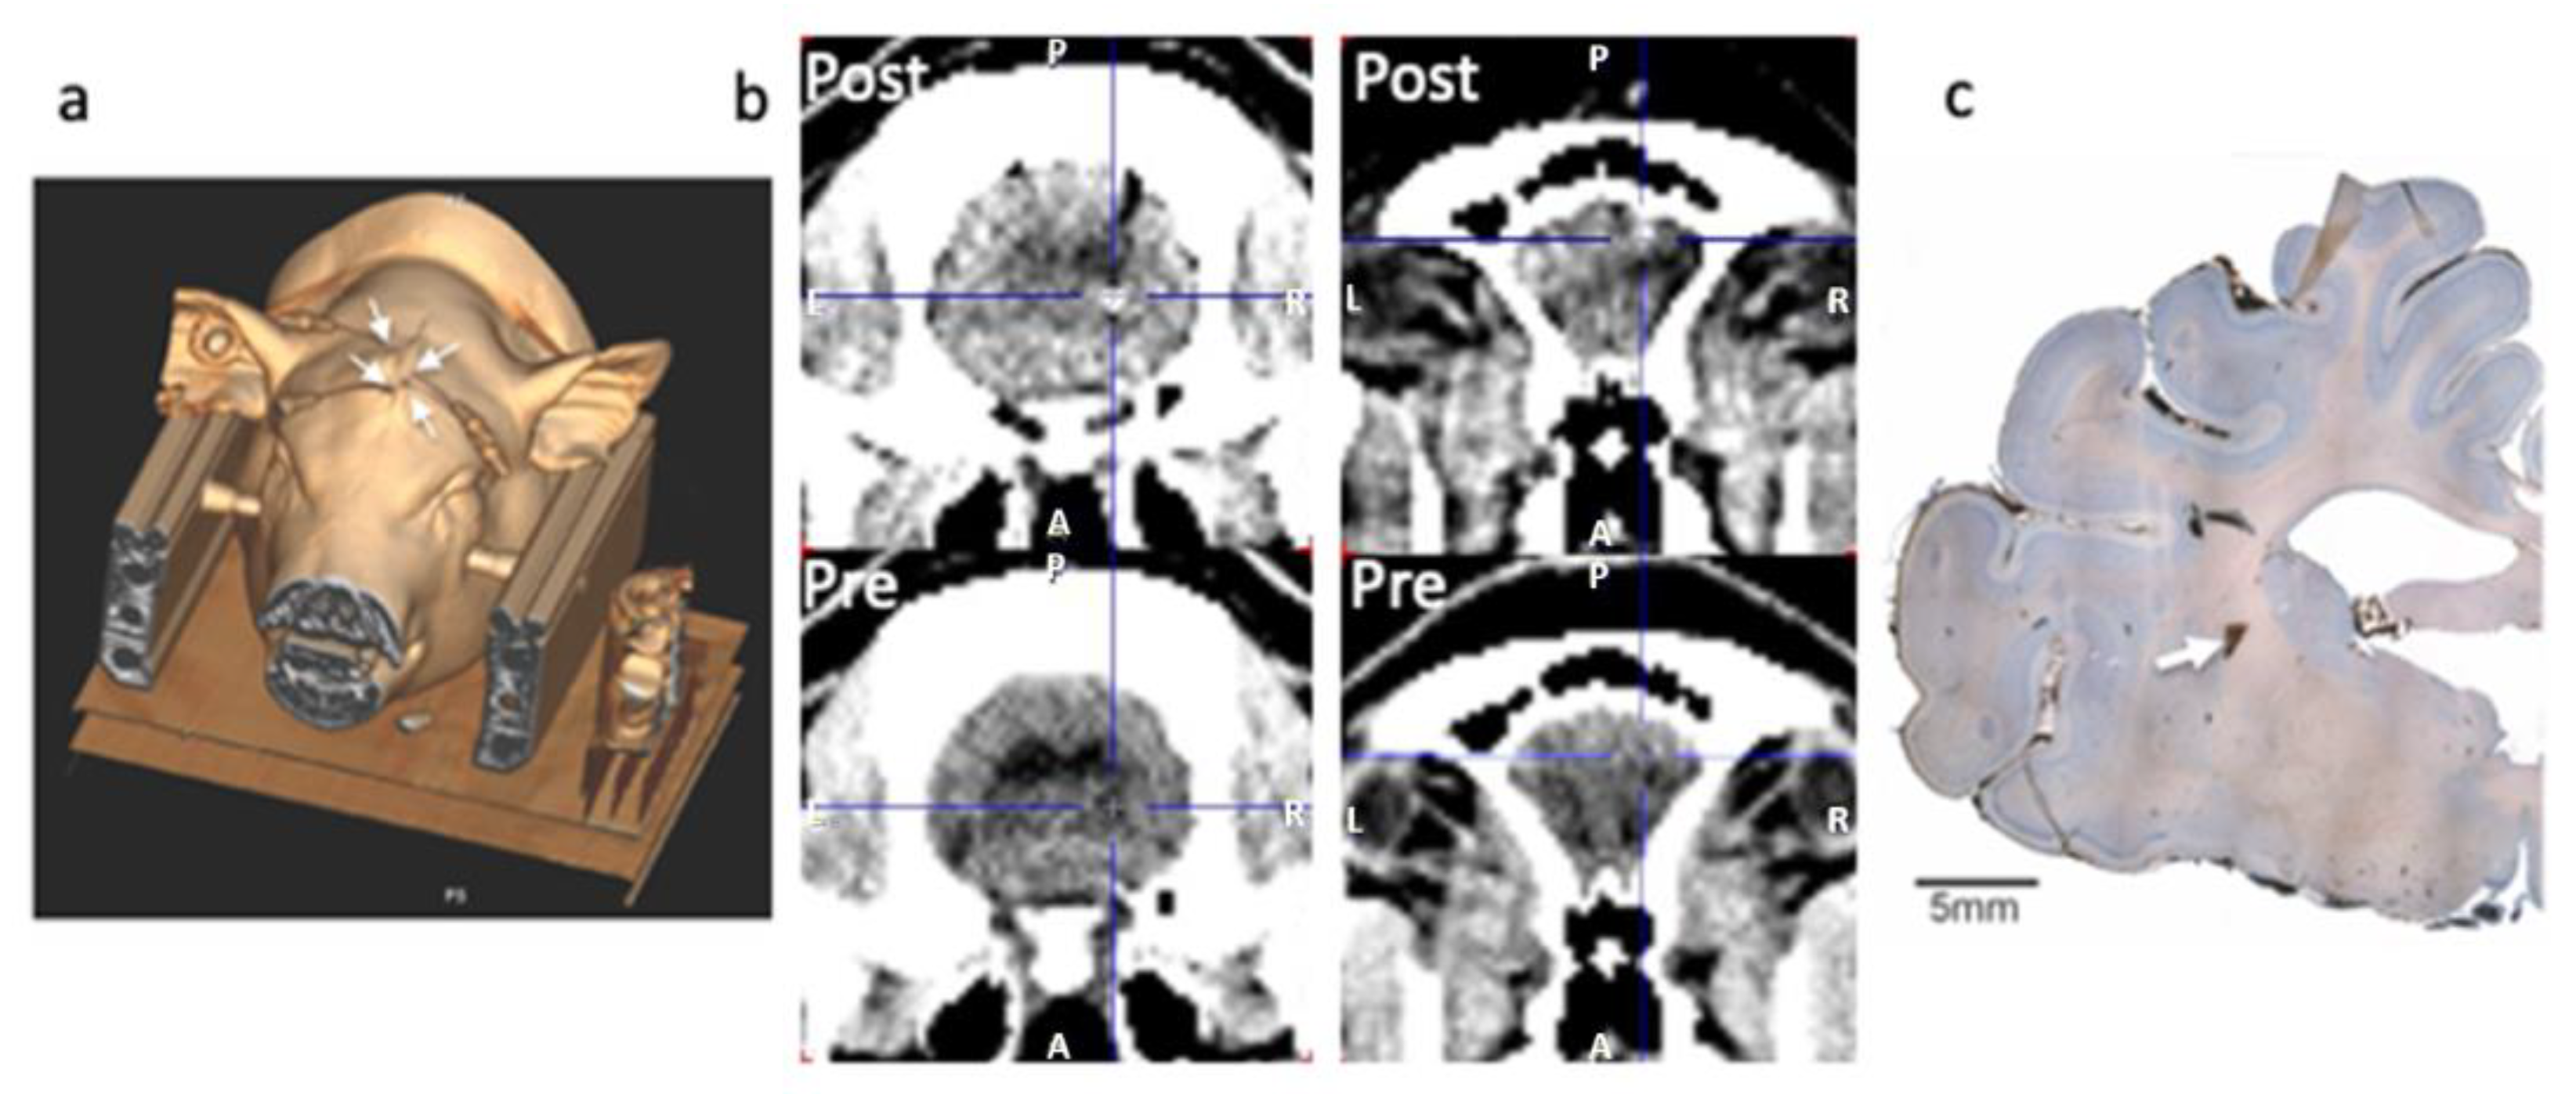

2.2. Experimental Setup

2.3. Tomography

2.4. PET Data Analysis

2.5. HPLC Analysis of Dialysates